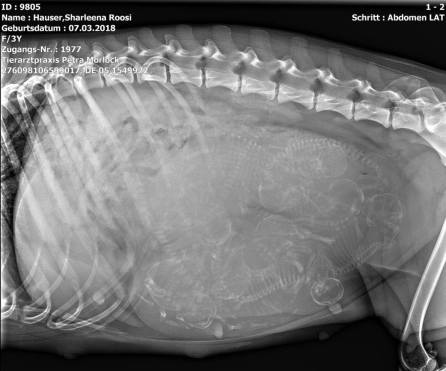

Röntgen 11.05.2021

Wir haben 10 Welpen gezählt!

Roosi´s Babybauch